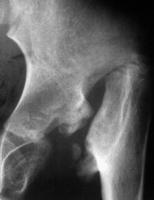

Abbildung 1: Linkes Hüftgelenk. St. p. eitriger Coxitis: Femurkopf und Schenkelhals sind "weggeschmolzen", das Femur stützt sich nur an der Darmbeinschaufel ab.